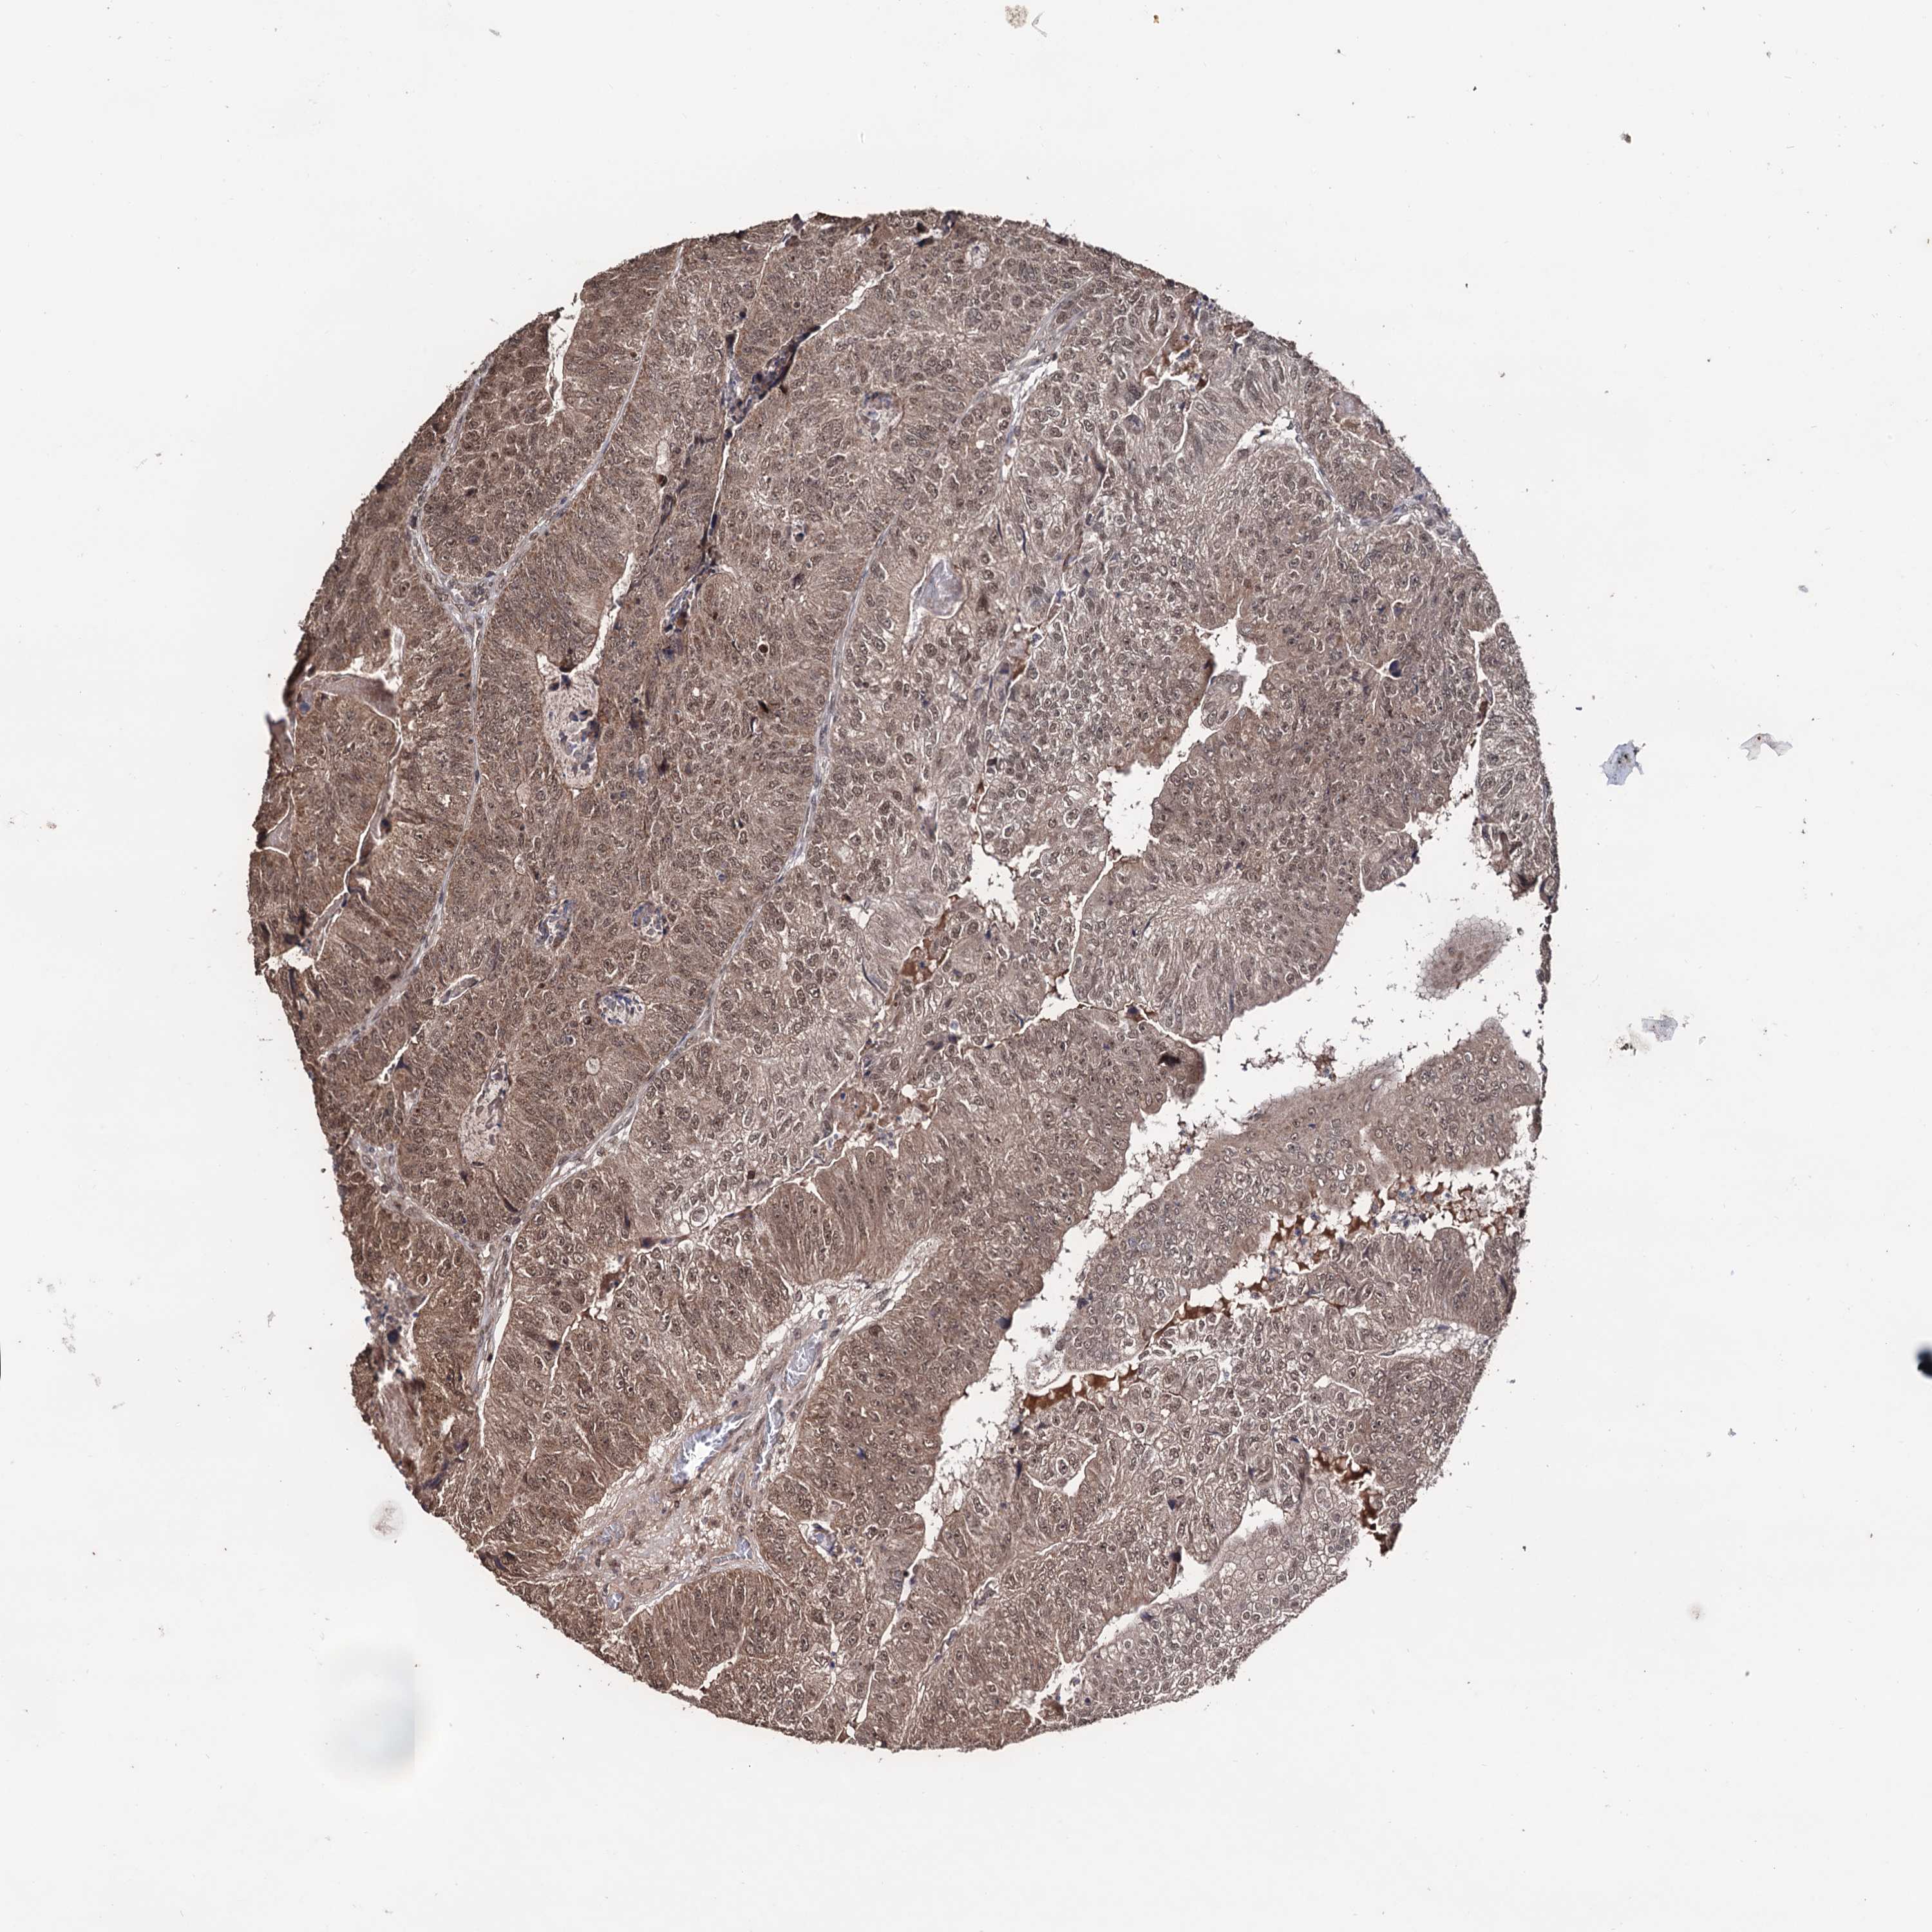

CANCER COLORECTAL CANCER Show tissue menu

Colorectal cancer

Human cancer

Colon adenocarcinoma